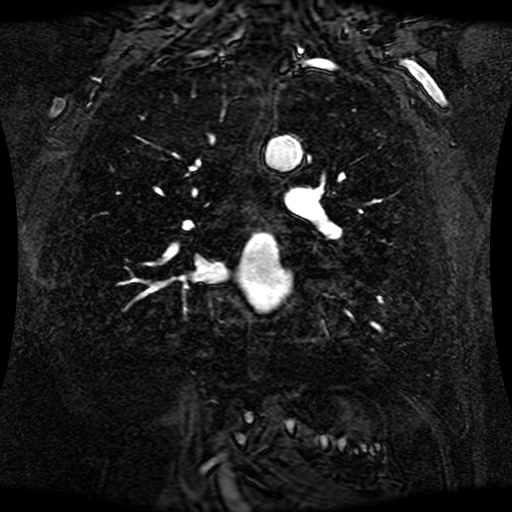

These magnetic resonance angiography (MRA) images show coronal slices acquired from consecutive anteroposterior positions within the torso. The study was performed on a 1.5T General Electric (GE) Signa imaging system with gadolinium-contrast-enhancement for visualization of the cardiopulmonary vasculature. The pulse sequence used was a 3D time-of-flight fast spoiled gradient recalled acquisition in steady state (FSPGR, TR=6.3, TE=1.4, NEX=1, FOV = 40cm, slice thickness = 1.2mm).

This sample image contains 76 frames. It is available in DICOM format (E1154S7I.dcm), as an animated GIF (E1154S7I.gif), as .ogg, .mp4, .webm, and .swf animations (one of which is shown above), or as individual PNG-format frames (see below).